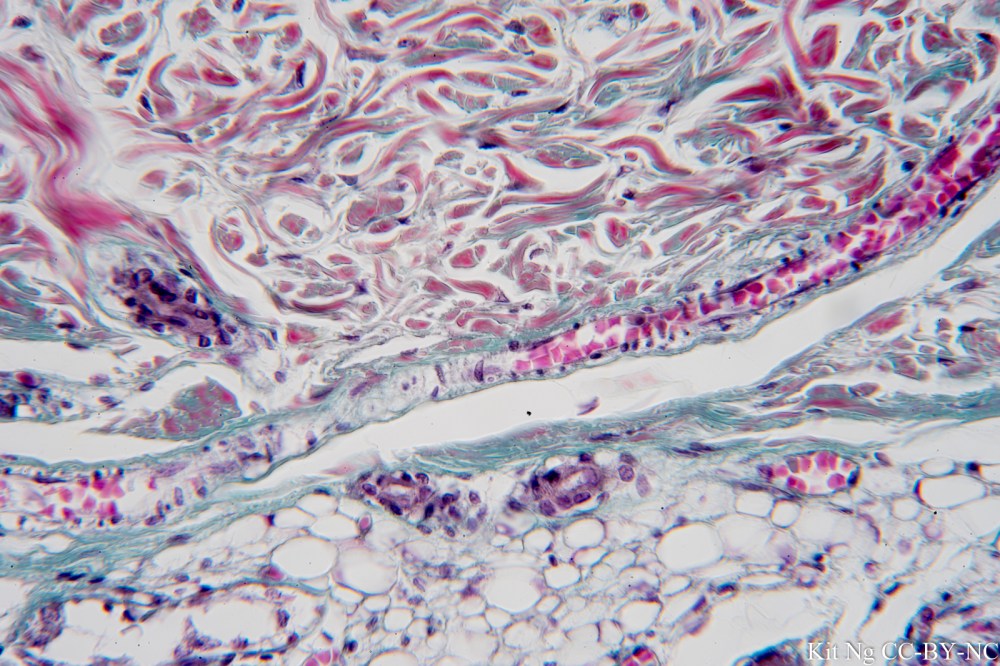

Dermis has two layers: papillary dermis and reticular dermis. The deeper reticular dermis is composed of mostly dense irregular connective tissue that makes it resistant to pulling forces in many directions. Structures that can be found in the dermis are: Messiner’s corpuscle, Pacinian corpuscle, hair follicle, arrector pili, sebaceous (oil) gland, and sweat gland.

Hypodermis is composed of mostly adipose tissue. It is also known as the subcutaneous layer and superficial fascia.

Under the hypodermis would be the deep fascia that wraps around the skeletal muscle.